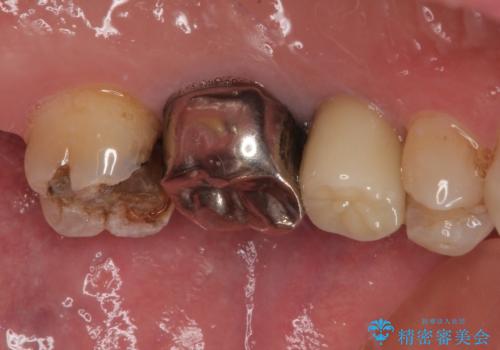

- 銀歯がとれたのでやり替えたいとのことで来院された患者様です。何度も同じ部位の銀歯の脱離を繰り返しており、メタルインレーの不適合も認めていたためオールセラミッククラウンにて補綴治療を行っていくことにしました。

拡大鏡視野下で、セラミックの被せもの、虫歯の除去を行い、オールセラミッククラウンに適した形に整えました。